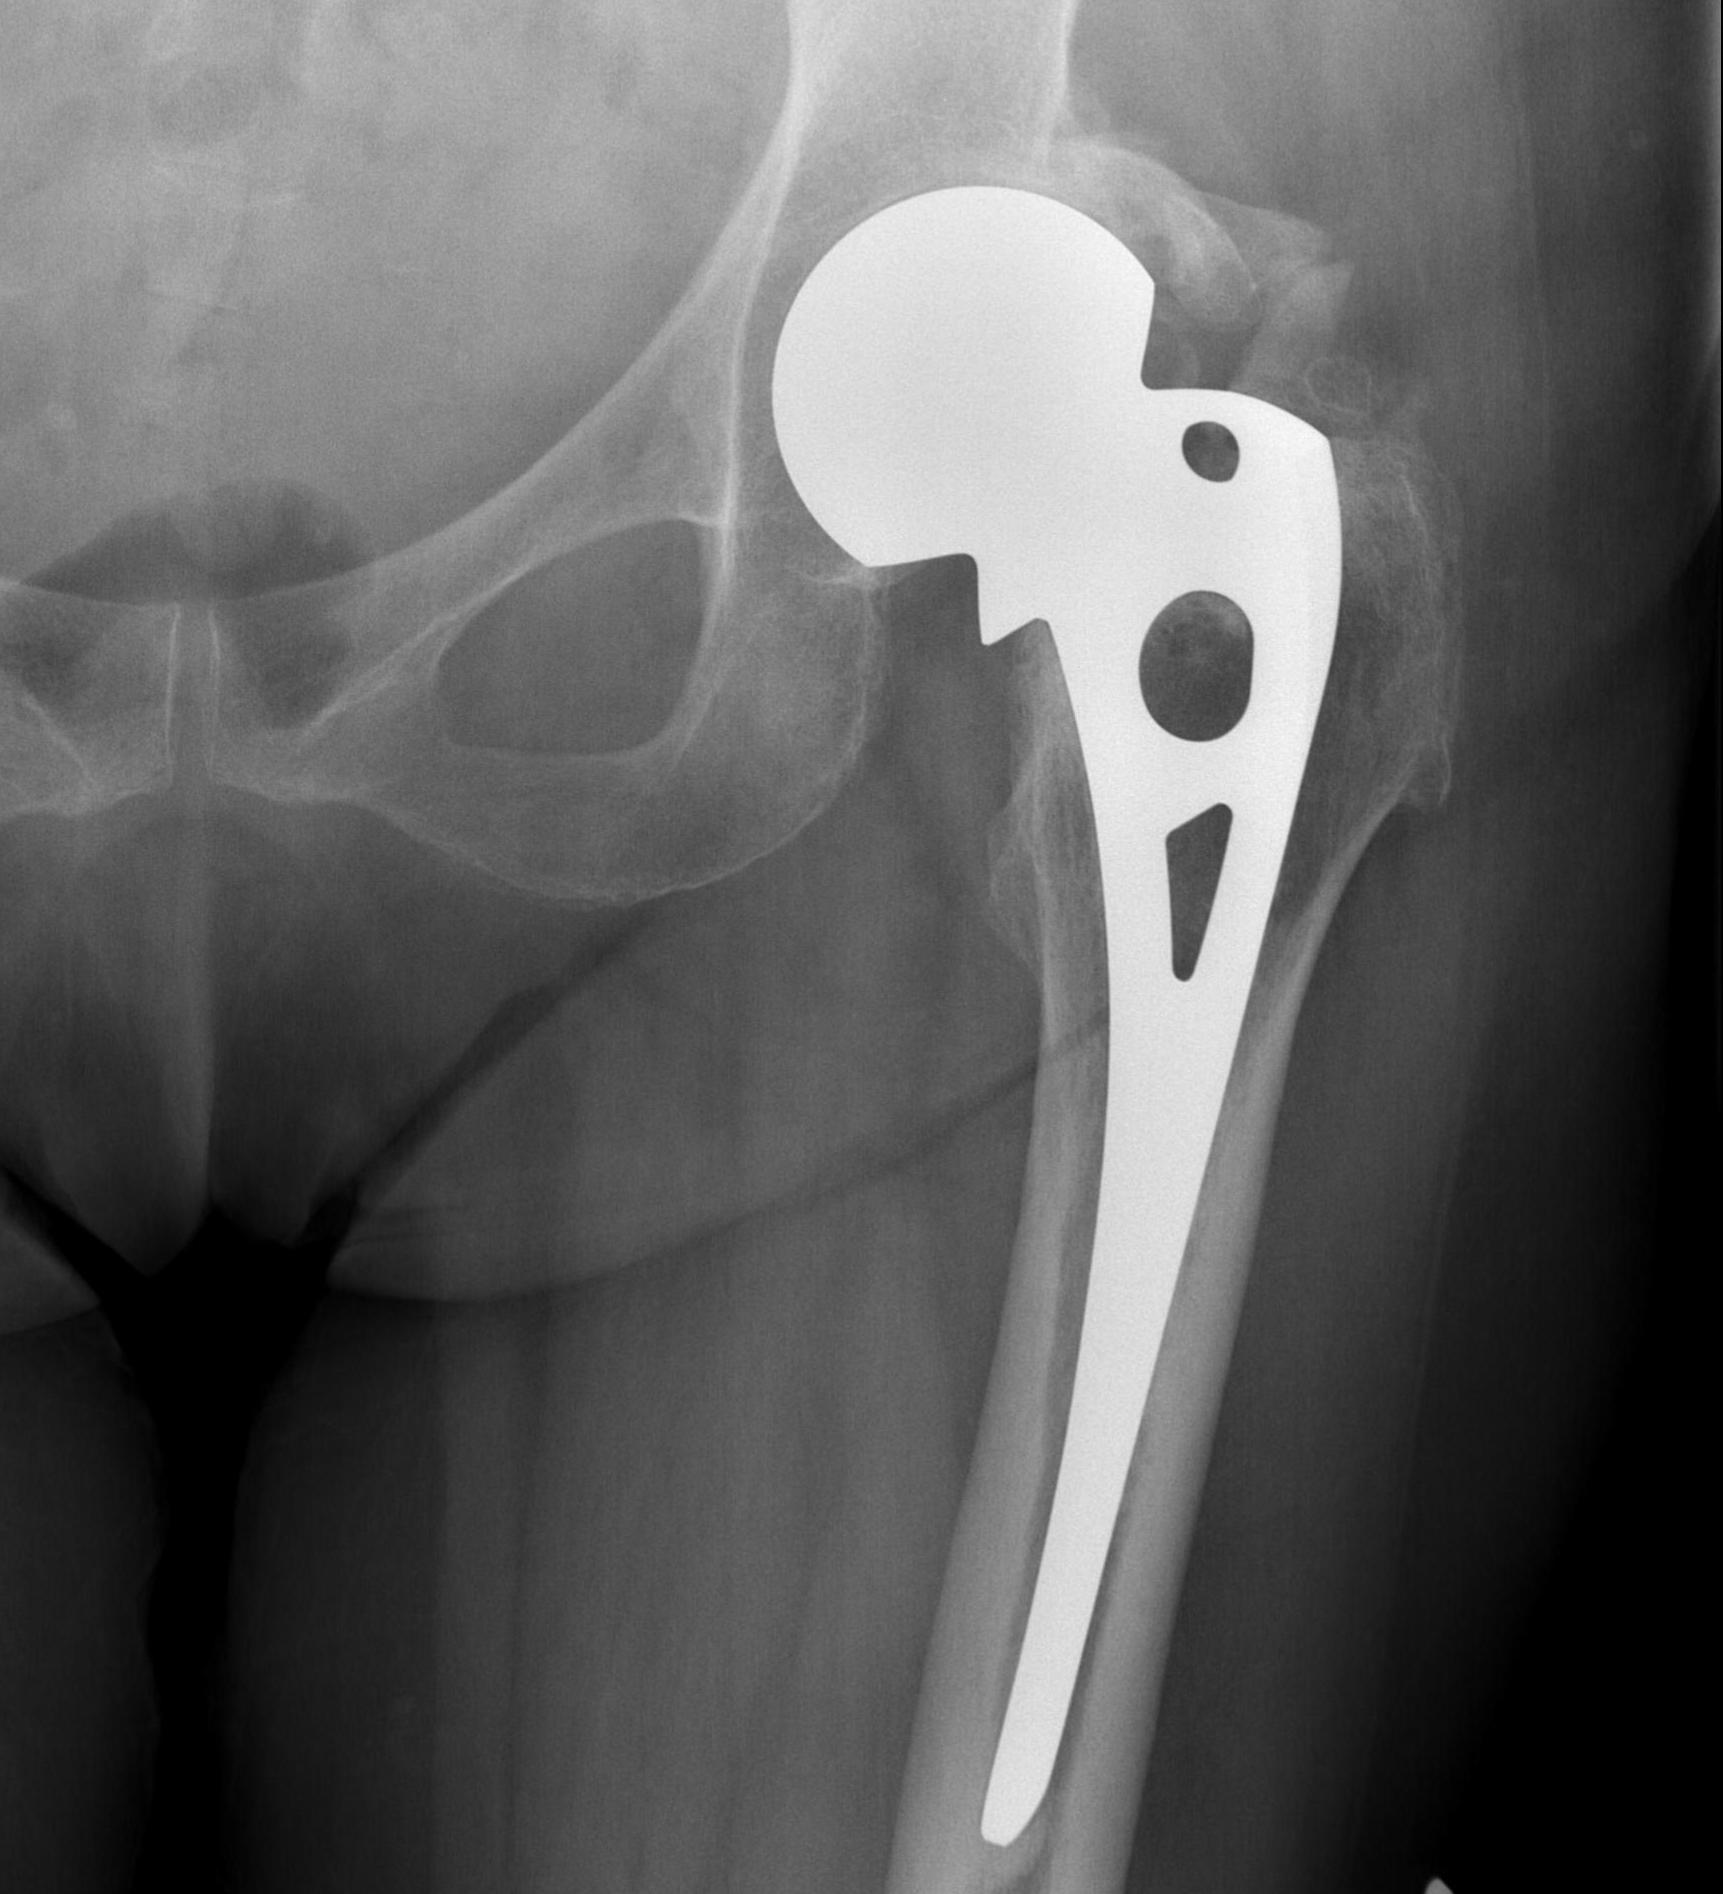

Cemented unipolar hemiathroplasty Uncemented bipolar hemiarthroplasty

Cement

- minimizes fracture risk in osteoporotic patients

- reduced risk thigh pain

- slightly increased cardiac risk with cement

- RCT of 400 patients

- cemented vs uncemented

- cemented HA had better early mobility

- cemented HA had significantly lower mortality

- no difference in complication or revision rate